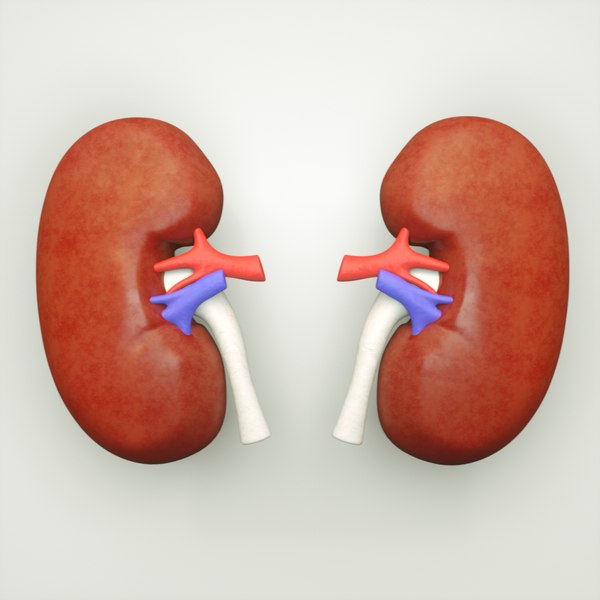

Строение почек человека: Фото и описание